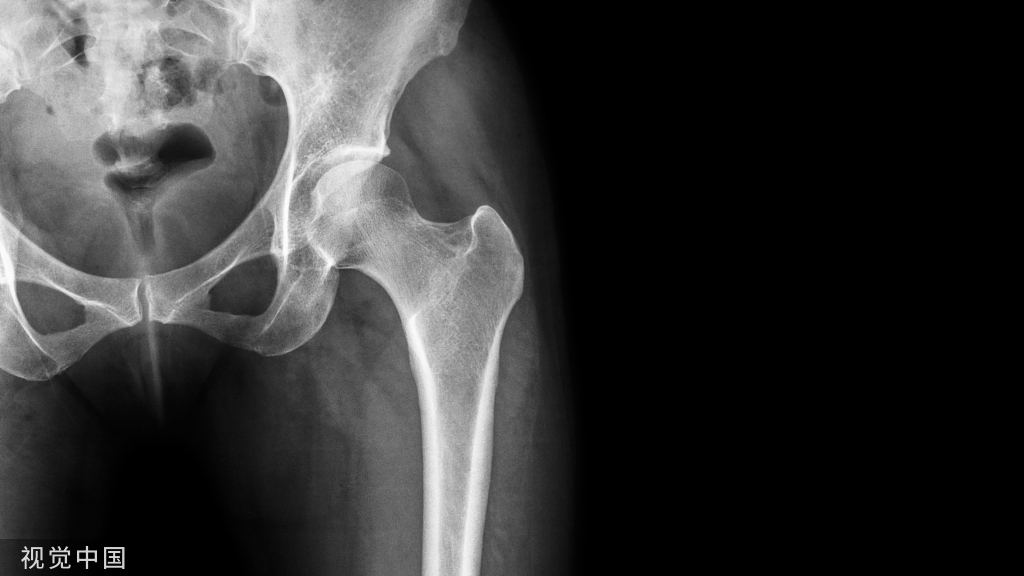

尺骨撞击综合征患者行尺骨短缩截骨术术前术后X线片